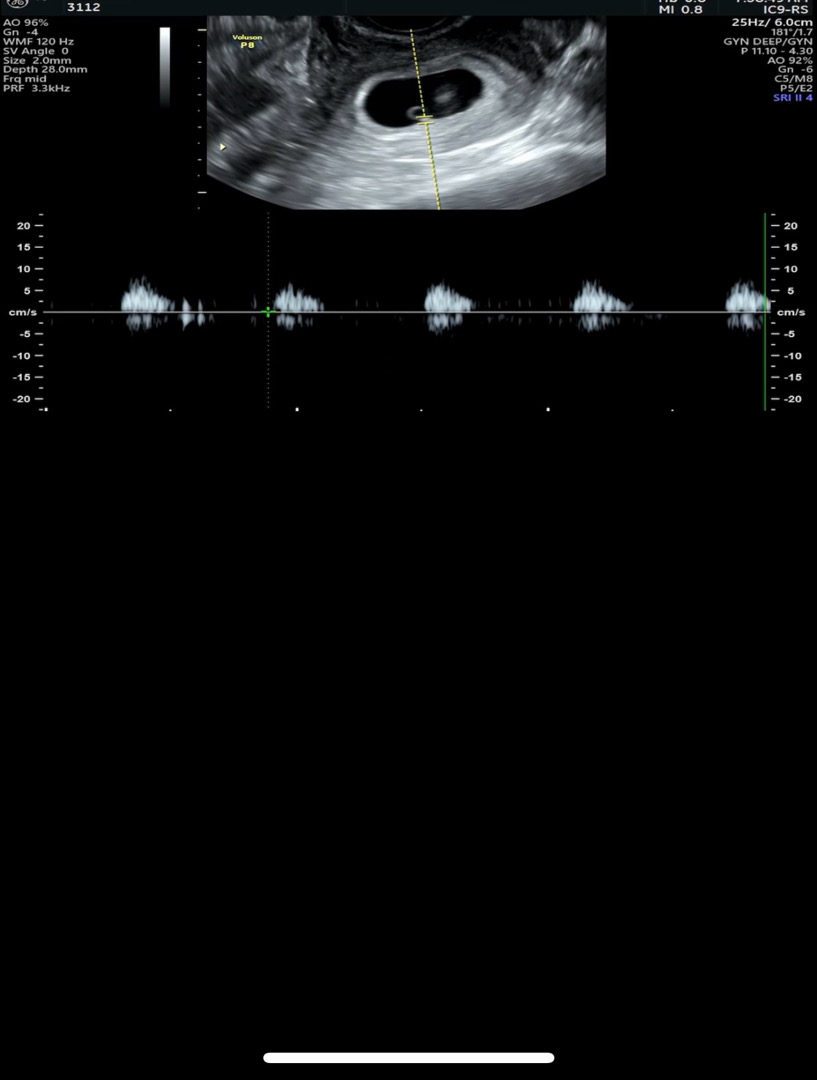

아기는 지금 네이버주수로만 5주6일이고 자연임신이라서 정확한주수는아직 모른데요~ 아기는 3mm이고 심장소리는오늘처음들엇는데 95~102bpm나오는듯해요 ㅠㅠ 조금느리긴하다는데 그말에 조금불안하네요 다음주에 또 가는데 ㅠㅠ

원래 5주에 80-103나오구 갈수록 빨라진데요! 너무 걱종하지마요! 다음주에는 더 빨라질거에요!